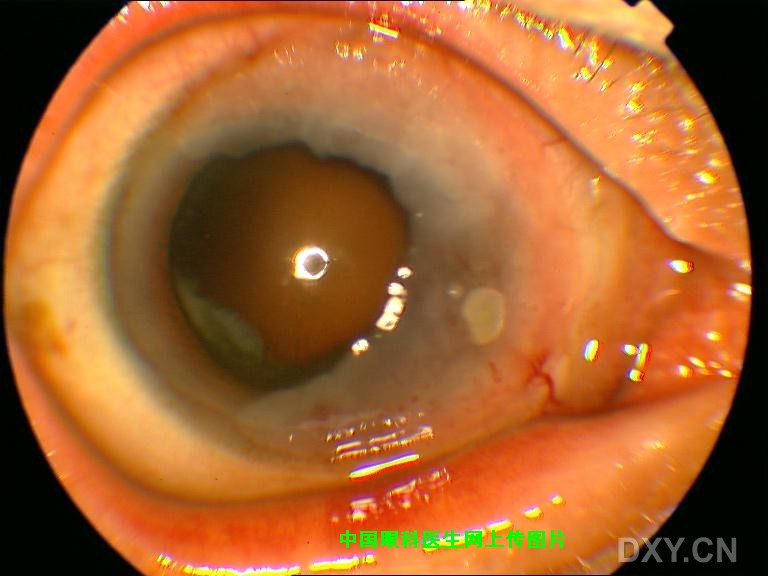

老年男性,左眼略有不适来诊,否认外伤,以前也没有因此就医。 结膜除局部充血外,没有异常增生或隆起;角膜如图,表面没有着色,轻度隆起,KP(-)。病人有酒糟鼻。

裂隙灯下所见

还请大家仔细看图,鼻侧角膜并没有溃疡,更没有局部变薄,而是轻度扁平隆起,再重申一下整个角膜没有染色。 |

该病人的确存在睑板腺功能不良,并且除局部眼药外,也给与口服抗生素。给大家一个线索,查查文献是否为角结膜上皮内上皮癌,又名BOWEN病? |

患者角膜上皮没有染色-----因此,没有溃疡。 患者没有明显症状-----因此,可以排除蚕蚀性角膜溃疡等有明显症状的疾病。 患者的情况比较象变性------在[眼科全书]第三版中有关于角膜变性与营养不良的概念的解释。 必须注意的是:在病变区可以看到有新生血管,且病变明显区有浅粉红色样改变。 我曾经接诊过角结膜鳞状细胞癌的病人,当时病人的病变为全角膜缘都有,宽约3mm,使眼睛呈“鱼眼”样外观(我回去找一找照片,如果还有,这两天发就到帖子上。)。所以综合考虑,我会认为是鳞状细胞癌。 |

qizhieye wrote: 这是我以前的患者图

非常感谢您所提供的图片,从形态上看,的确与我所报道的病例极为相像,随之而来的是诊断上的困惑,我们诊断为Bowen病(角膜上皮内上皮癌)的主要依据如下: 1.睑裂区角膜缘病变,灰白色半透明隆起,发展缓慢且症状轻微; 2.手术当中非常容易剥离,说明病变没有突破基底膜; 3.当然最有发言权的应该是病理所见(金标准);我曾将病理图片发到丁香园病理讨论区,但回应者不多,看来还是得请咱们眼科特别是病理方面的同行来给大家解释一下该病例的病理图片。 另外如果可能也请您将您所报道病例的术后情况以及病理所见提供给大家。

该例患者是角结膜上皮内肿瘤(conjunctiva-cornea intraepithelial neoplasia,CCIN ), 国内名称较多, 不统一,如:角结膜原位癌;Bowen病;角结膜上皮内上皮癌;结膜上皮内肿瘤等, 目前国际上已经普遍采用角结膜上皮内肿瘤(CCIN)来统一命名。 假如你进入pubmed查资料,用Bowen病是查不出的。我2004年在麦阿密眼表研究中心学习,那里有不少该病患者。我开始说这是Bowen disease,没有人明白什么病,后来查了资料,才知道国际上没有如此说法。 |